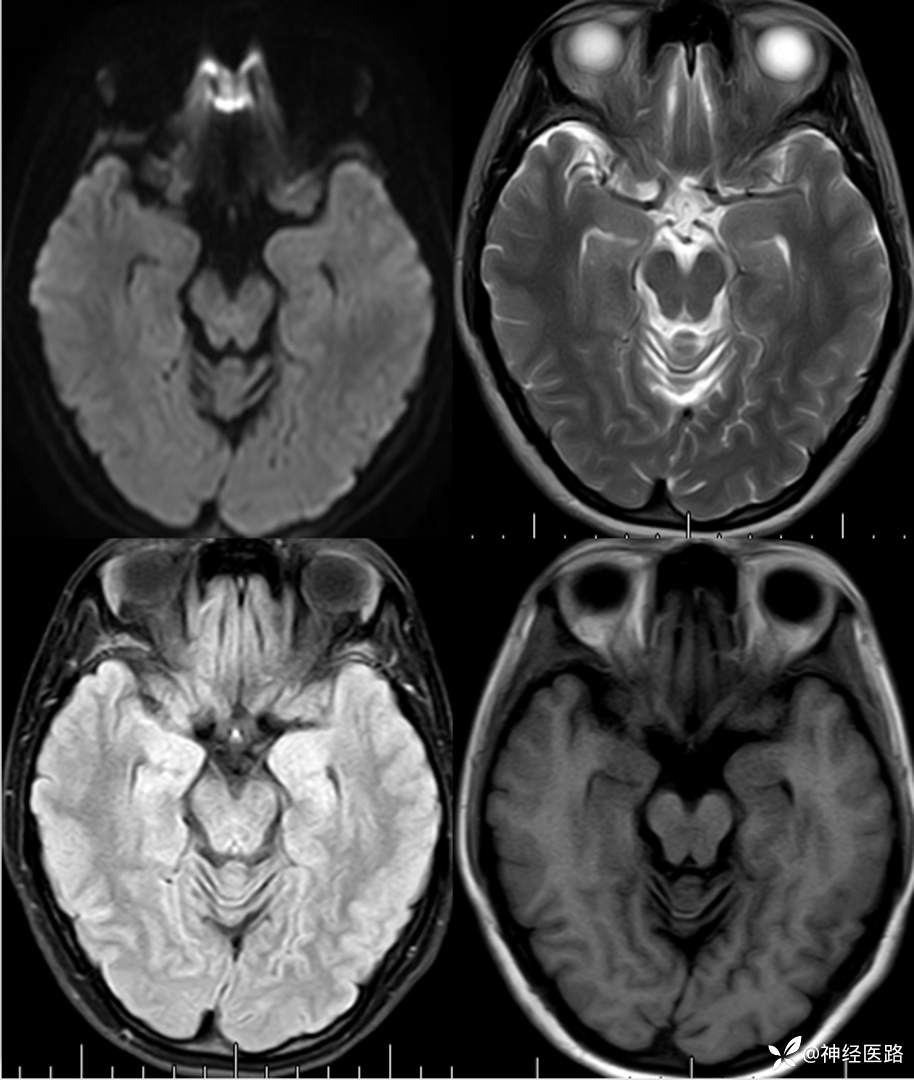

辅助检查:头部磁共振: 1.左侧额叶及右侧顶叶白质内高信号,请结合临床及相关检查。2.双侧小脑半球脑萎缩。3.部分颅骨信号增高。